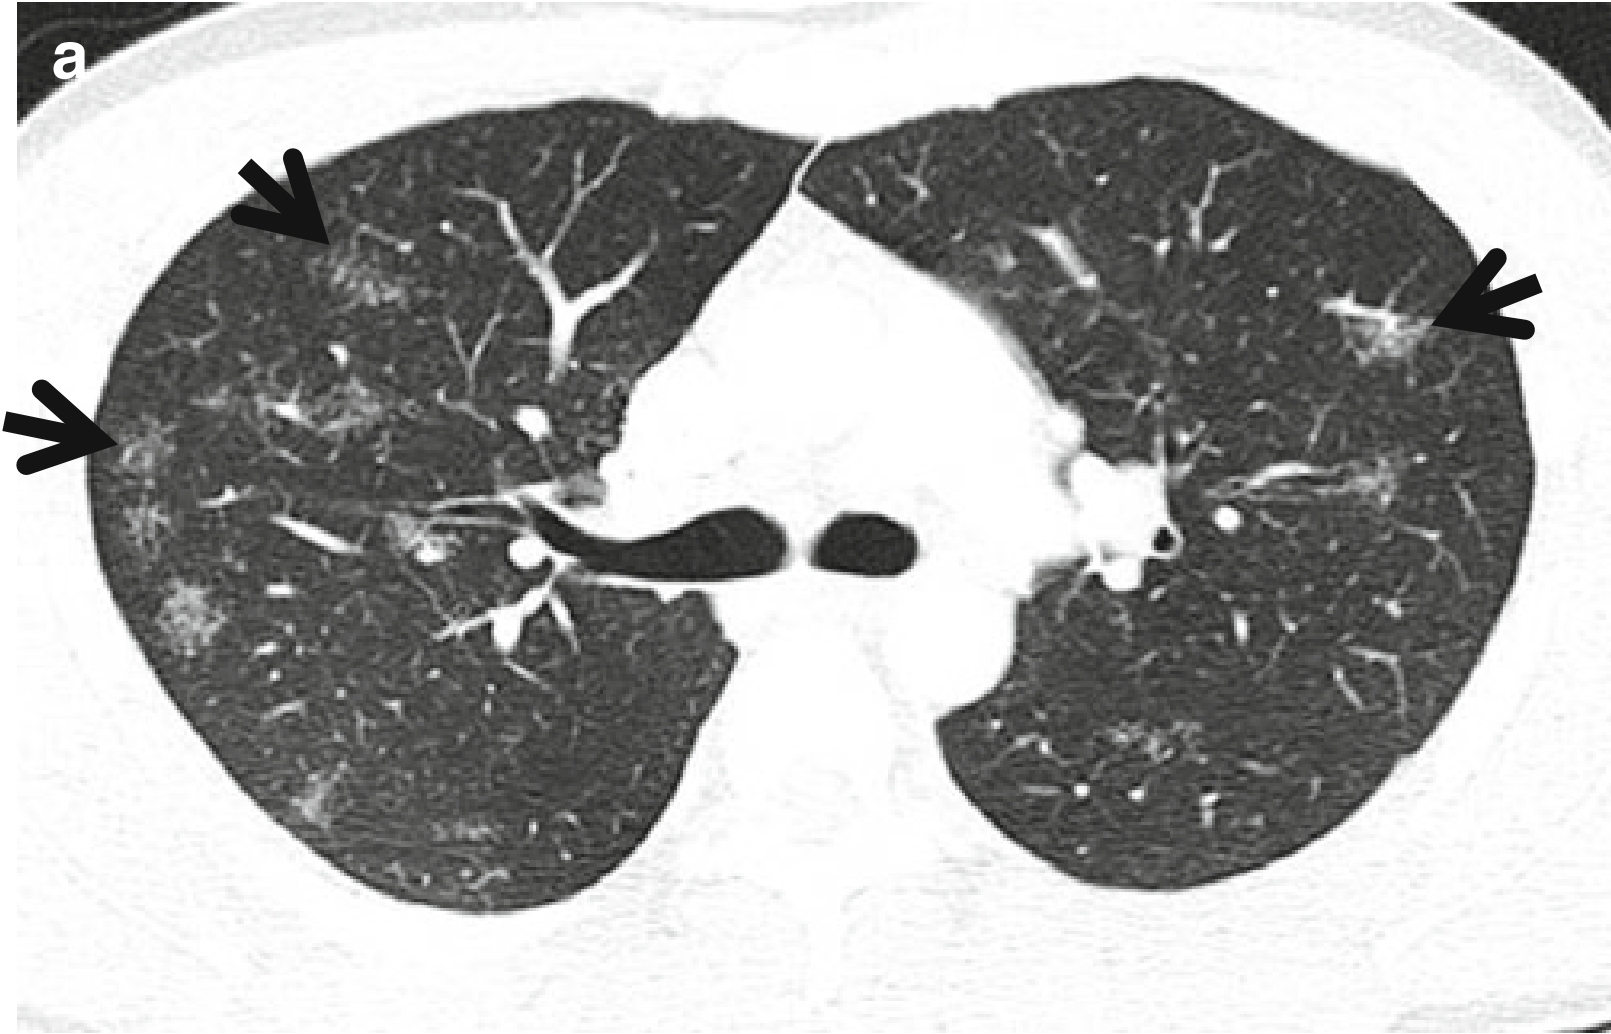

CT表现:CT表现为上叶和下叶背段簇状的单发或多发结节伴星系征,或星系征不伴有淋巴结肿大、树芽征,均支持肺结核的诊断,而非肺结节病(图2和图3)。

图3 CT星系征。男,53岁,活动性肺结核患者。薄层CT扫描(层厚=2.5mm)分别于主动脉弓水平(a)和奇静脉弓(b)水平肺窗示双肺上叶和左肺下叶背段的星系征(箭头所示)。